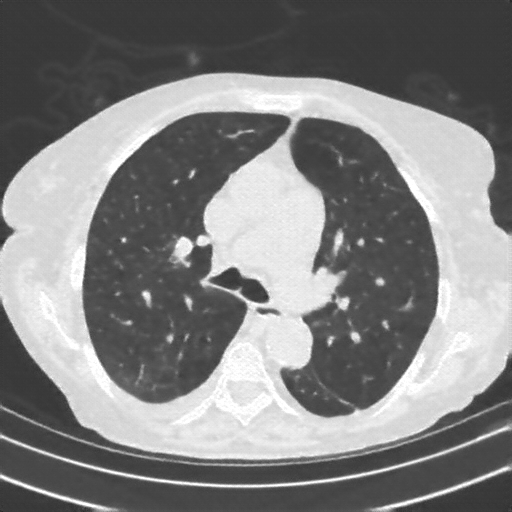

Targeted Slice 70 - Lung Window Analysis (Generated vs Real Venous)

0.583

Lung SSIM

161.5

Lung RMSE

72.4

Lung MAE

Average Lung Window Metrics Across All Slices (153 slices) - Generated vs Real Venous

0.553

Lung SSIM (Avg)

147.1

Lung RMSE (Avg)

69.0

Lung MAE (Avg)

Generated VENOUS CT scan (A→B translation)

Lung window (WL -600, WW 1500 β†’ Low βˆ’1350, High +150)